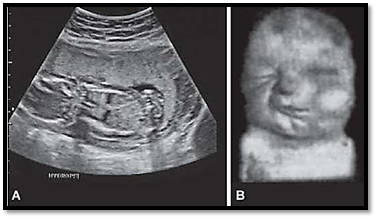

Deformities due to abnormal intrauterine moulding can arise because of maternal or fetal conditions. Dislocation of the hip joint, and clubfoot result from oligohydramnios. Fetuses with abnormalities of the musculoskeletal system may have positional deformities. Multiple pregnancies or breech presentation can also result in deformities. A well renal recognized syndrome, Potter syndrome (Figs 4A and B) is associated with renal agenesis leading to oligohydramnios, which in turn can cause fetal deformation and pulmonary hypoplasia.

Figs 4A and B: An example of a deformation is the potter syndrome. Note the severe oligohydramnios seen on ultrasound (A) and (B) a fetus with Potter syndrome